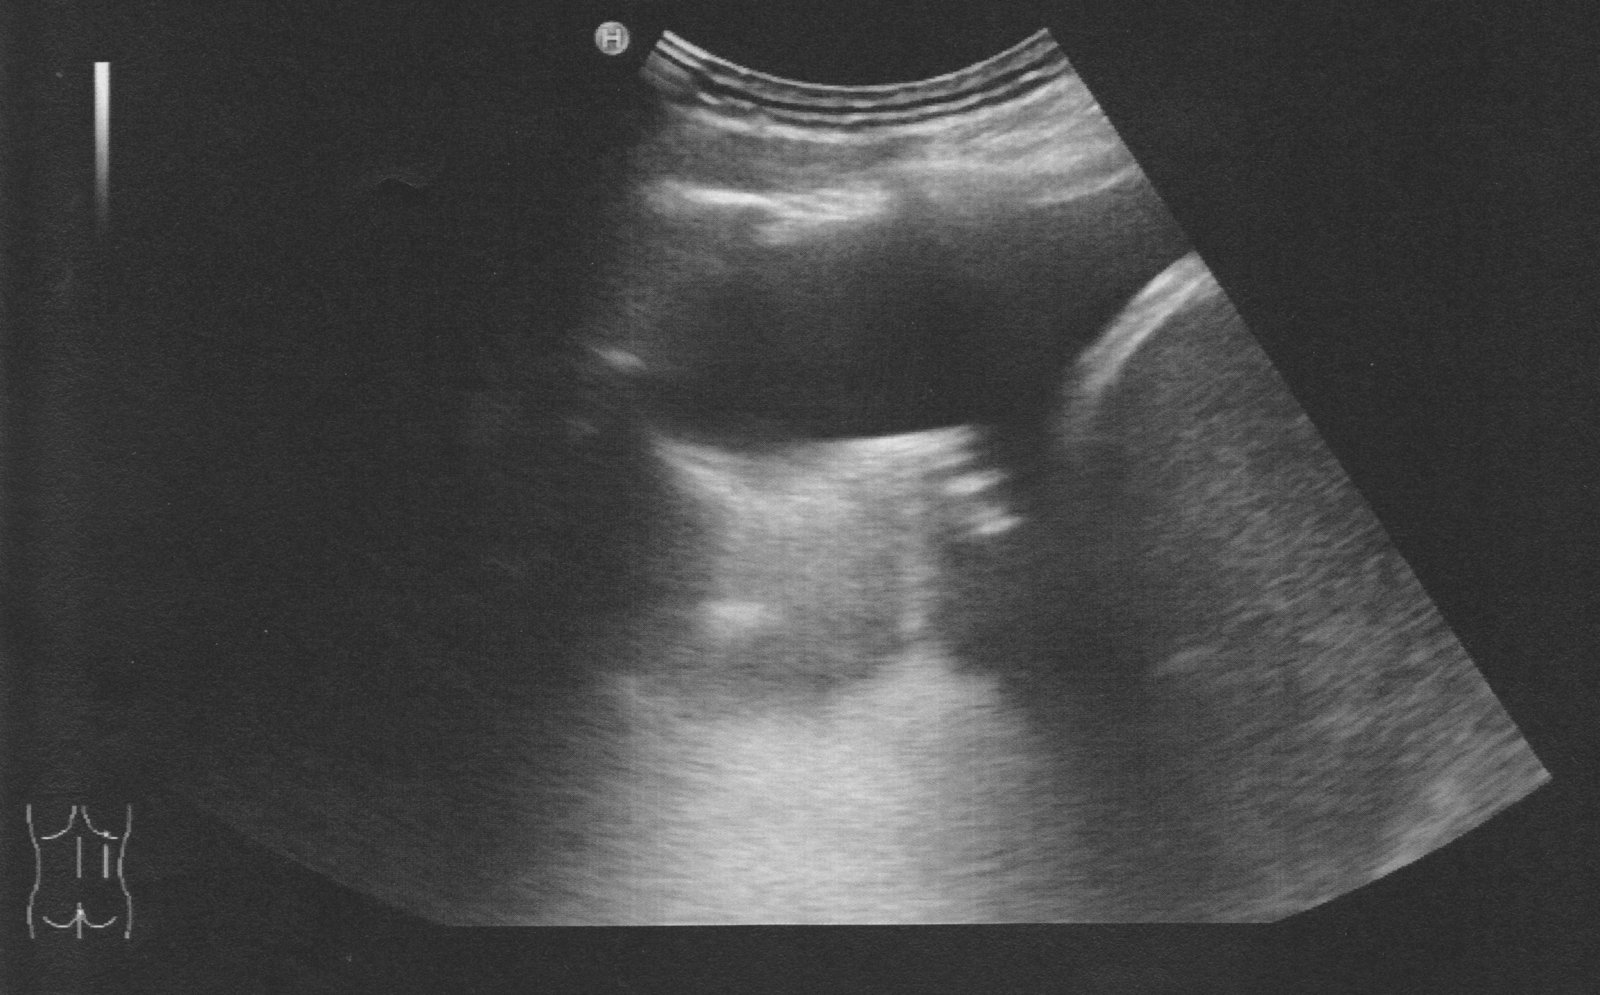

Point-of-care ultrasound, e.g., FAST scan

IVC ultrasound

Point-of-care ultrasound (e.g., FAST, POCUS for suspected AAA, POCUS for early pregnancy)